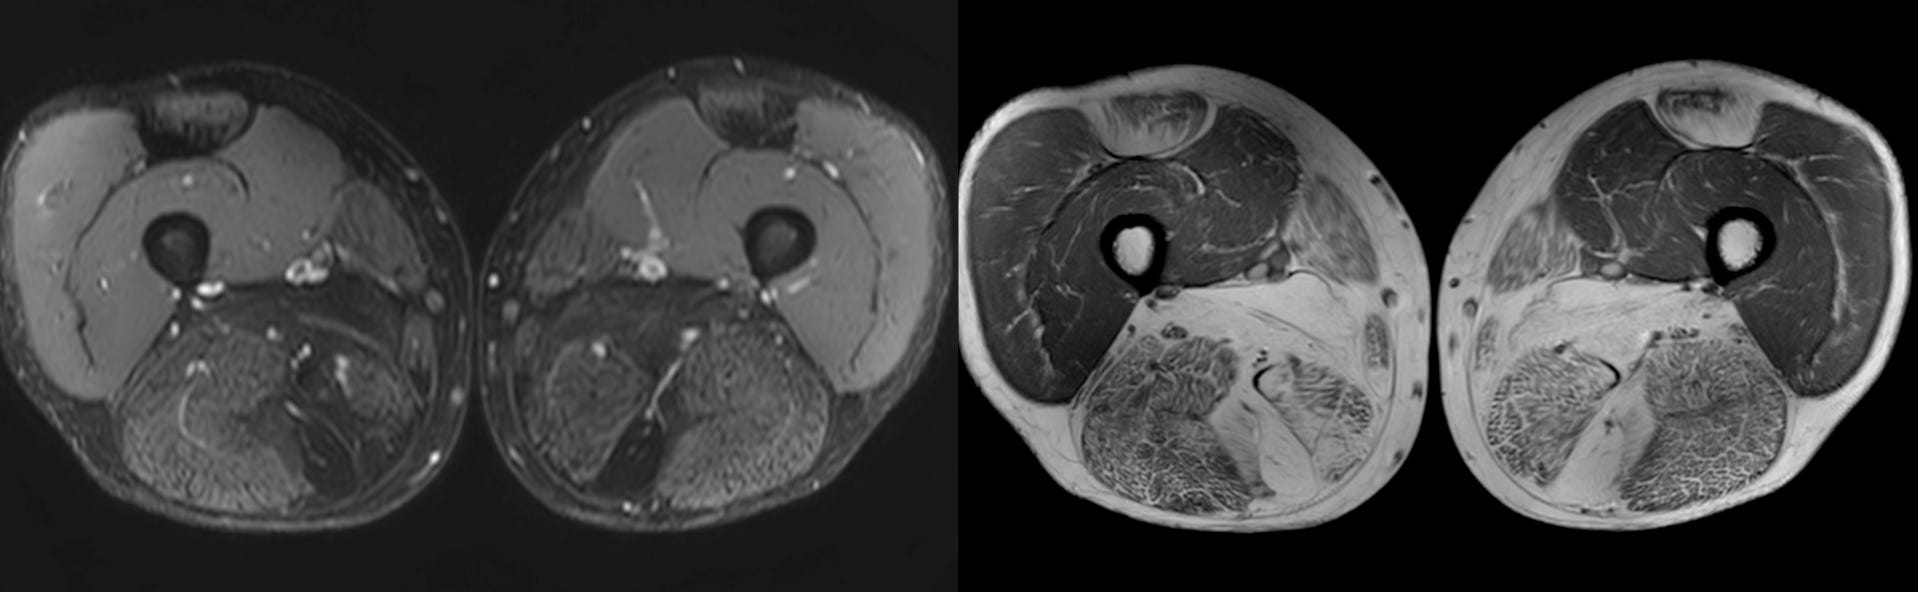

Case 63: The Honeycomb Pattern of Myositis

What is striking is the honeycomb pattern

The video describes the classic honeycomb pattern in this patient’s muscles and the implications and compares with the other patterns - fascial and peripheral/foggy described earlier in previous videos.